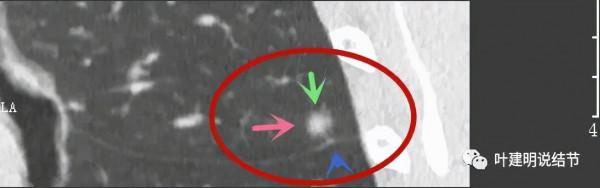

那麼進一步靶掃描這3處結節的細節又是如何的呢?

主病灶此層是磨玻璃,但有明顯血管進入病灶(桔色箭頭)

病灶表現不平,密度雜亂,輪廓相對清楚

有明顯的分葉徵(磚色箭頭)以及磨玻璃成分(綠色箭頭)和偏實性的成分(粉紅色箭頭)

上圖也示病灶有明顯的分葉徵(磚色箭頭)以及磨玻璃成分(綠色箭頭)和偏實性的成分(粉紅色箭頭)

上圖層面居然見到病灶周圍的細毛刺徵(紫色箭頭),有實性成分(粉色箭頭)

密度雜亂,輪廓清楚

實性成分較多,有明顯磨玻璃成分

上圖示微血管有血管彎徵,與病灶界限不清,實性成分佔比較高

病灶密度不均,感覺有點僵硬

影象後處理與重建的影象顯示了更清楚的資訊,顯示主病灶(下稱A病灶)分葉(磚色箭頭)、有磨玻璃成分(綠色箭頭)以及實性成分(粉紅色箭頭)

病灶鄰近胸膜,密度雜亂

病灶實性佔比較多,輪廓清楚,胸膜有牽拉(藍色箭頭)

三維重建示病灶圓形類圓形